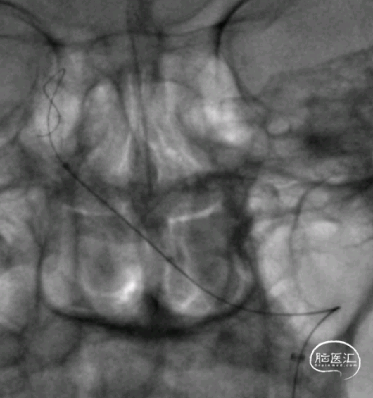

术后影像:

术后颅脑CT平扫:

术后3月余复查:

动脉瘤愈合,支架内血流通畅。